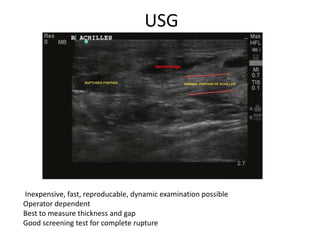

USG

Inexpensive, fast, reproducable, dynamic examination possible

Operator dependent

Best to measure thickness and gap

Good screening test for complete rupture